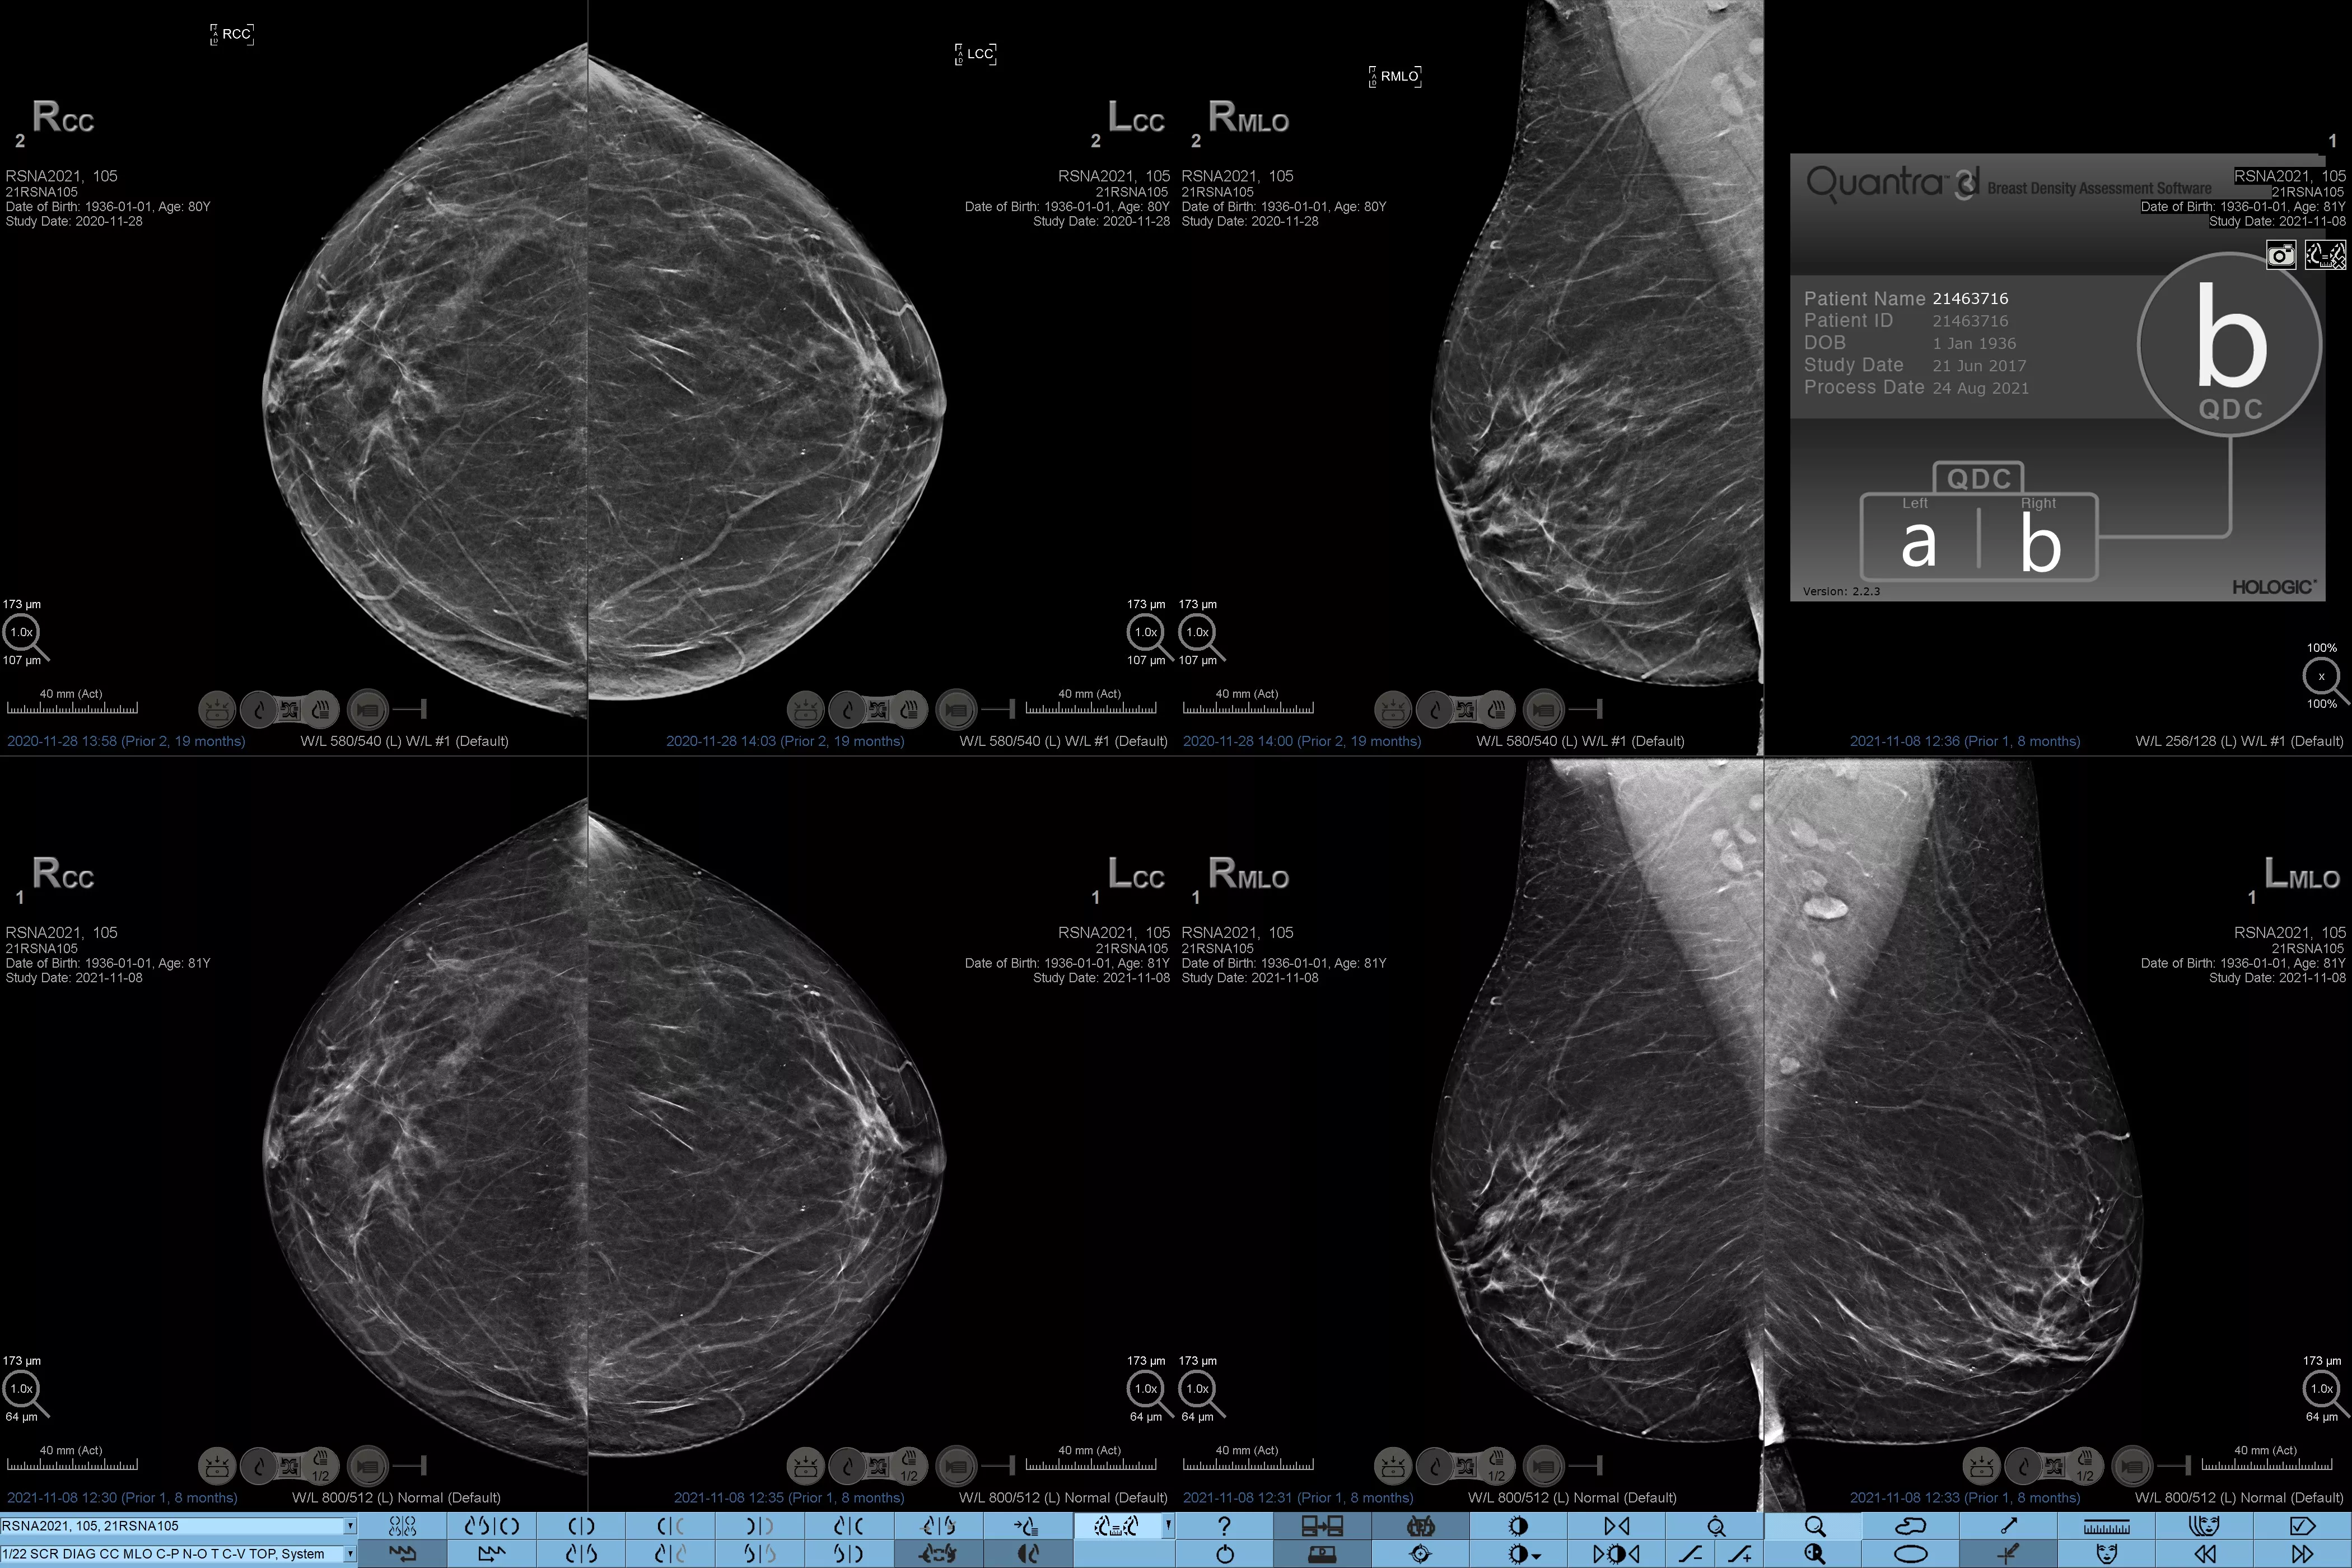

Higher breast density is known to increase a woman’s risk for breast cancer.1 The need for accurate, unbiased analysis is therefore critical. Powered by machine learning, Quantra technology software analyses both 2D™ and tomosynthesis images for distribution and texture of parenchymal tissue. It categorises breasts in four breast composition categories consistent with guidance from the American College of Radiology (ACR) BI-RADS Atlas 5th Edition.2

Objective machine learning algorithm that assigns breast density category based on analysis of breast tissue texture and patterns.

Quantra software’s unbiased algorithm analyse both 2D and tomosynthesis images to support your analysis by:

• Overcoming subjectivity in visual assessment, providing more consistent, and more reliable scoring.*

• Elevating the standard of care and standardises reporting.

*Scores are based on ACR BI-RADS categories, in line with the revised guidance by the American College of Radiation (ACR) BI-RADS Atlas 5th Edition. This accounts for pattern and texture, compared with volume, when determining density.

8. Breast composition categories as described in ACR BI-RADS Atlas.